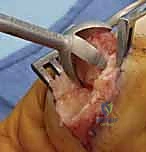

- Tension Band Fixation: This is a biomechanically superior method, often considered the gold standard for small joint arthrodesis.

- Mechanism: It combines parallel Kirschner wires for rotational control with interosseous wiring for compression. The genius of this